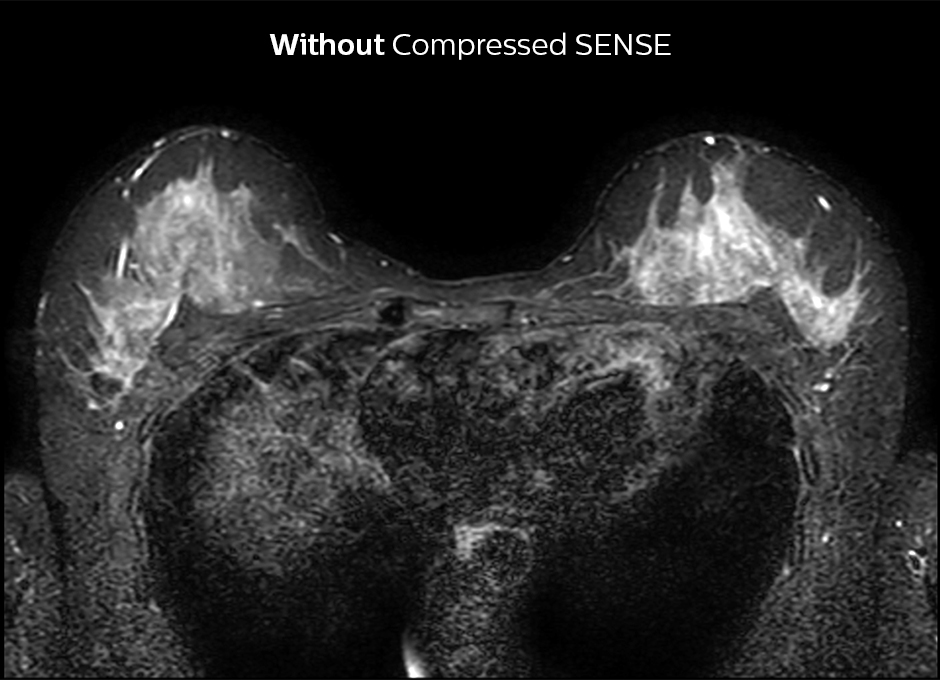

Accelerating 2D breast MRI

Compressed SENSE allows 29% shorter scan time with similar spatial resolution.

2D STIR, scan time 3:39 min, voxel size 1 x 1.25 x 3 mm.

2D STIR, scan time 2:36 min, voxel size 1 x 1.26 x 3 mm.